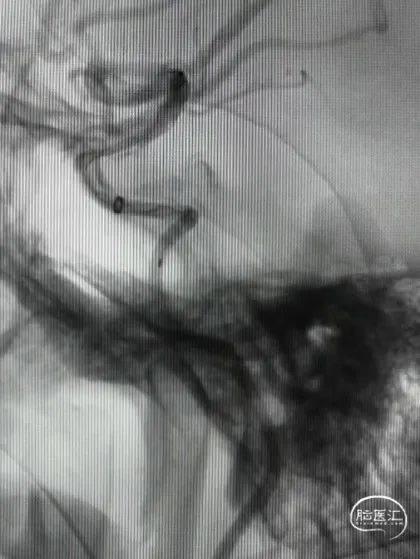

DSA造影(2024.11.07)

右侧颈内动脉起始段闭塞,动脉晚期可见颈动脉颅内段浅淡显影。

前交通动脉开放,右侧大脑中动脉显影良好。

右侧后交通动脉开放,右侧颈动脉颅内段浅淡显影。